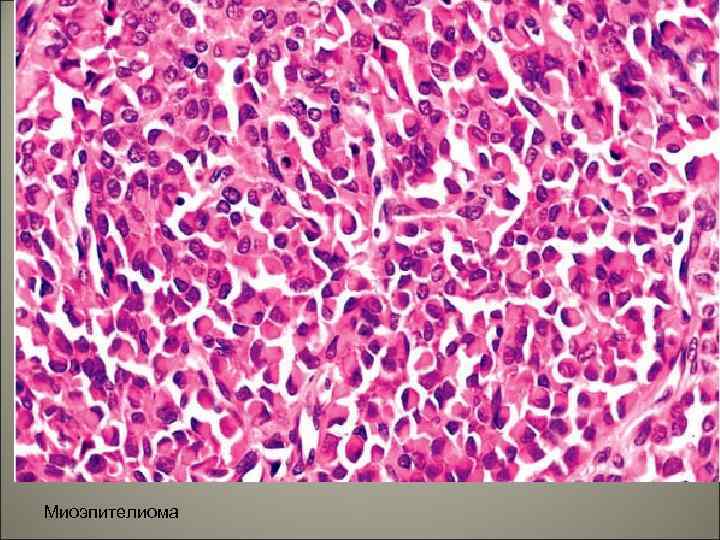

• Миоэпителиальная аденома. Составляет около 4% около эпителиальных опухолей слюнных желез. Чаще локализуется в околоушной слюнной железе, встречается в старшей возрастной группе от 40 до 80 лет, чаще у женщин.

• Макроскопически опухоль неправильной, узловатой формы, на разрезе представлена плотной белесоватой тканью. • Микроскопически опухоль состоит из веретенообразных, полигональных, плазмоцитоидных светлых клеток, формирующих анастомозирующие тяжи и солидные клеточные скопления, расположенные в миксоидном или гиалинизированном матриксе. Микроскопически выделяют три варианта: ретикулярный с тяжами миоэпителиальных клеток и миксоидным компонентом, солидный – с комплексами из плазмоцитоидных и светлых клеток и смешанный.

Миоэпителиома